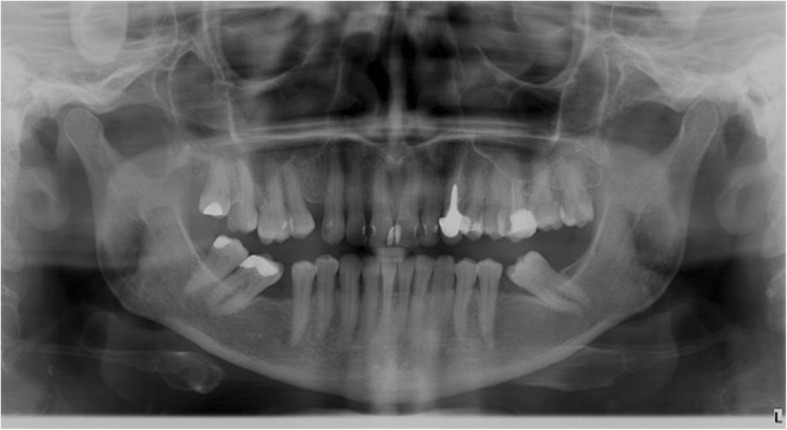

Moreover, a morphological classification of the mandibular cortical bone has been proceeded on panoramic radiographs. Mandibular cortical index (MCI) according to Klemetti et al. [20] was used to assess morphological changes in the inferior cortex of the mandible. Mandibular cortical shapes were analysed by observing the mandible distally from the mental foramina bilaterally and by categorizing them into one of the following three groups as previously described by Klemetti et al. [20]: “C1 – the endosteal margin of the cortex is even and sharp on both sides (Fig. 2); C2 - the endosteal margin shows semilunar defects (lacunar resorption) or endosteal cortical residues on one or both sides, mild to moderate cortex erosion (Fig. 3); C3 – the cortical layer forms heavy endosteal cortical residues and clearly porous, severely eroded cortex” (Fig. 4).

Fig. 3.

Panoramic radiograph with C2 category of MCI